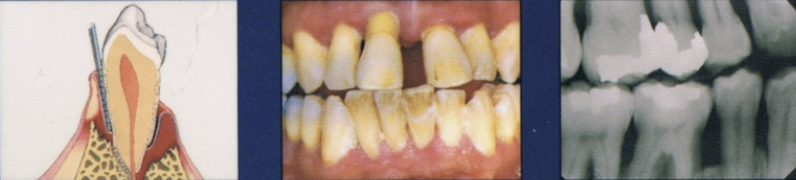

Describe early stage of periodontitis

Progression of gingival inflammation into deeper periodontal structures and alveolar bone crest

Slight bone loss

Slight loss of CT attachment + alveolar bone

Describe moderate stage of periodontal disease

More advanced stage of previous condition

Increased destruction of periodontal structures

Noticeable bone loss, support, and increase in mobility

Furcation involvement

Describe advanced stage of periodontal disease

Major loss of alveolar bone support

increased tooth mobility